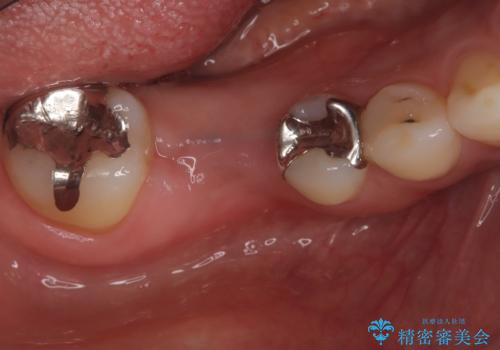

骨の量は十分あったため、比較的短期間で治療は終了しました。

安定した咬み合わせとなり、痛みもなく安心して噛めるようになりました。